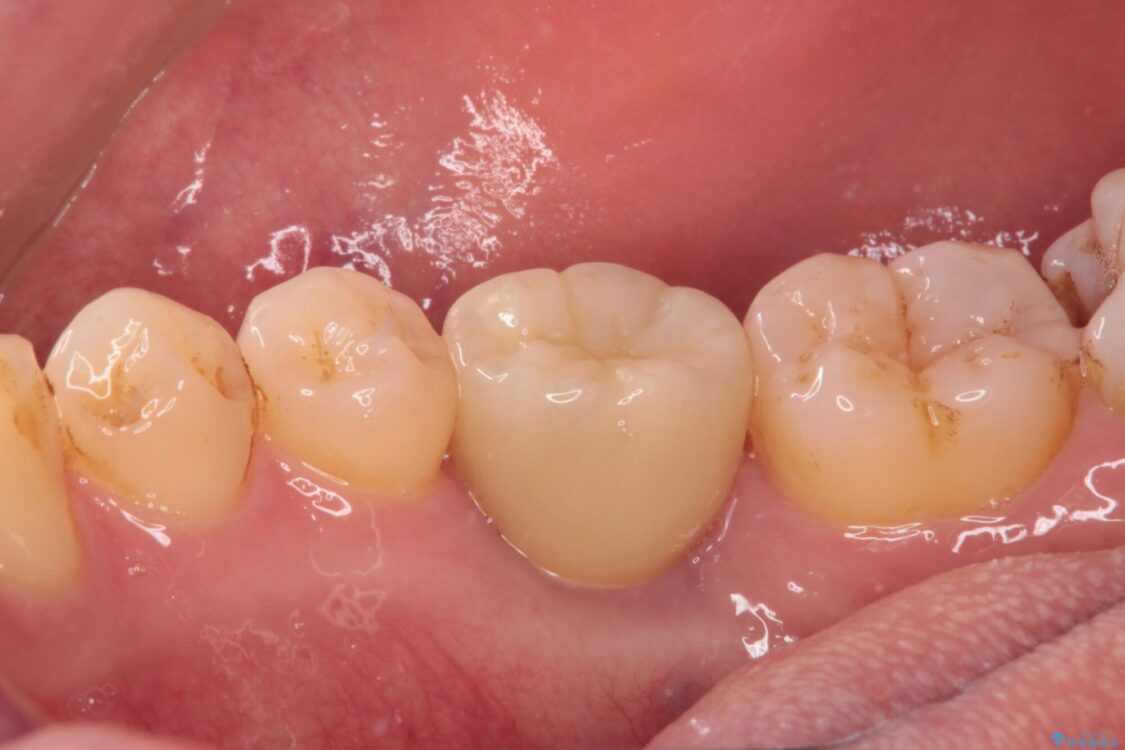

治療後

• 空いている時間を利用して通院 奥歯のインプラント治療 治療後画像